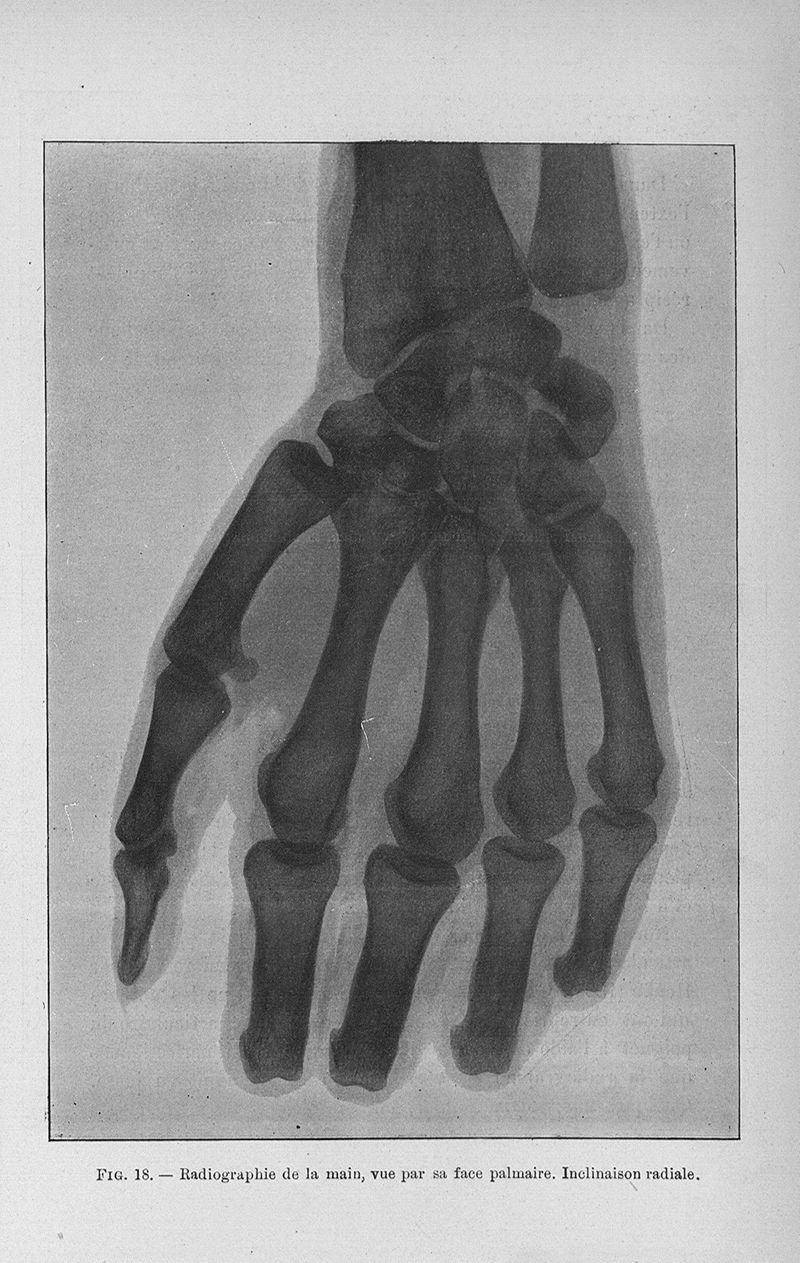

Cunéo, Bernard Joseph.

Exposé des titres et travaux

Paris, G. Steinheil, 1901.